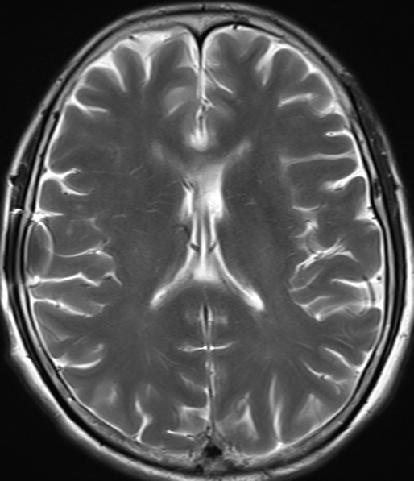

2013-8-2 MRI

2013-8-2 CT

腰穿脑压240